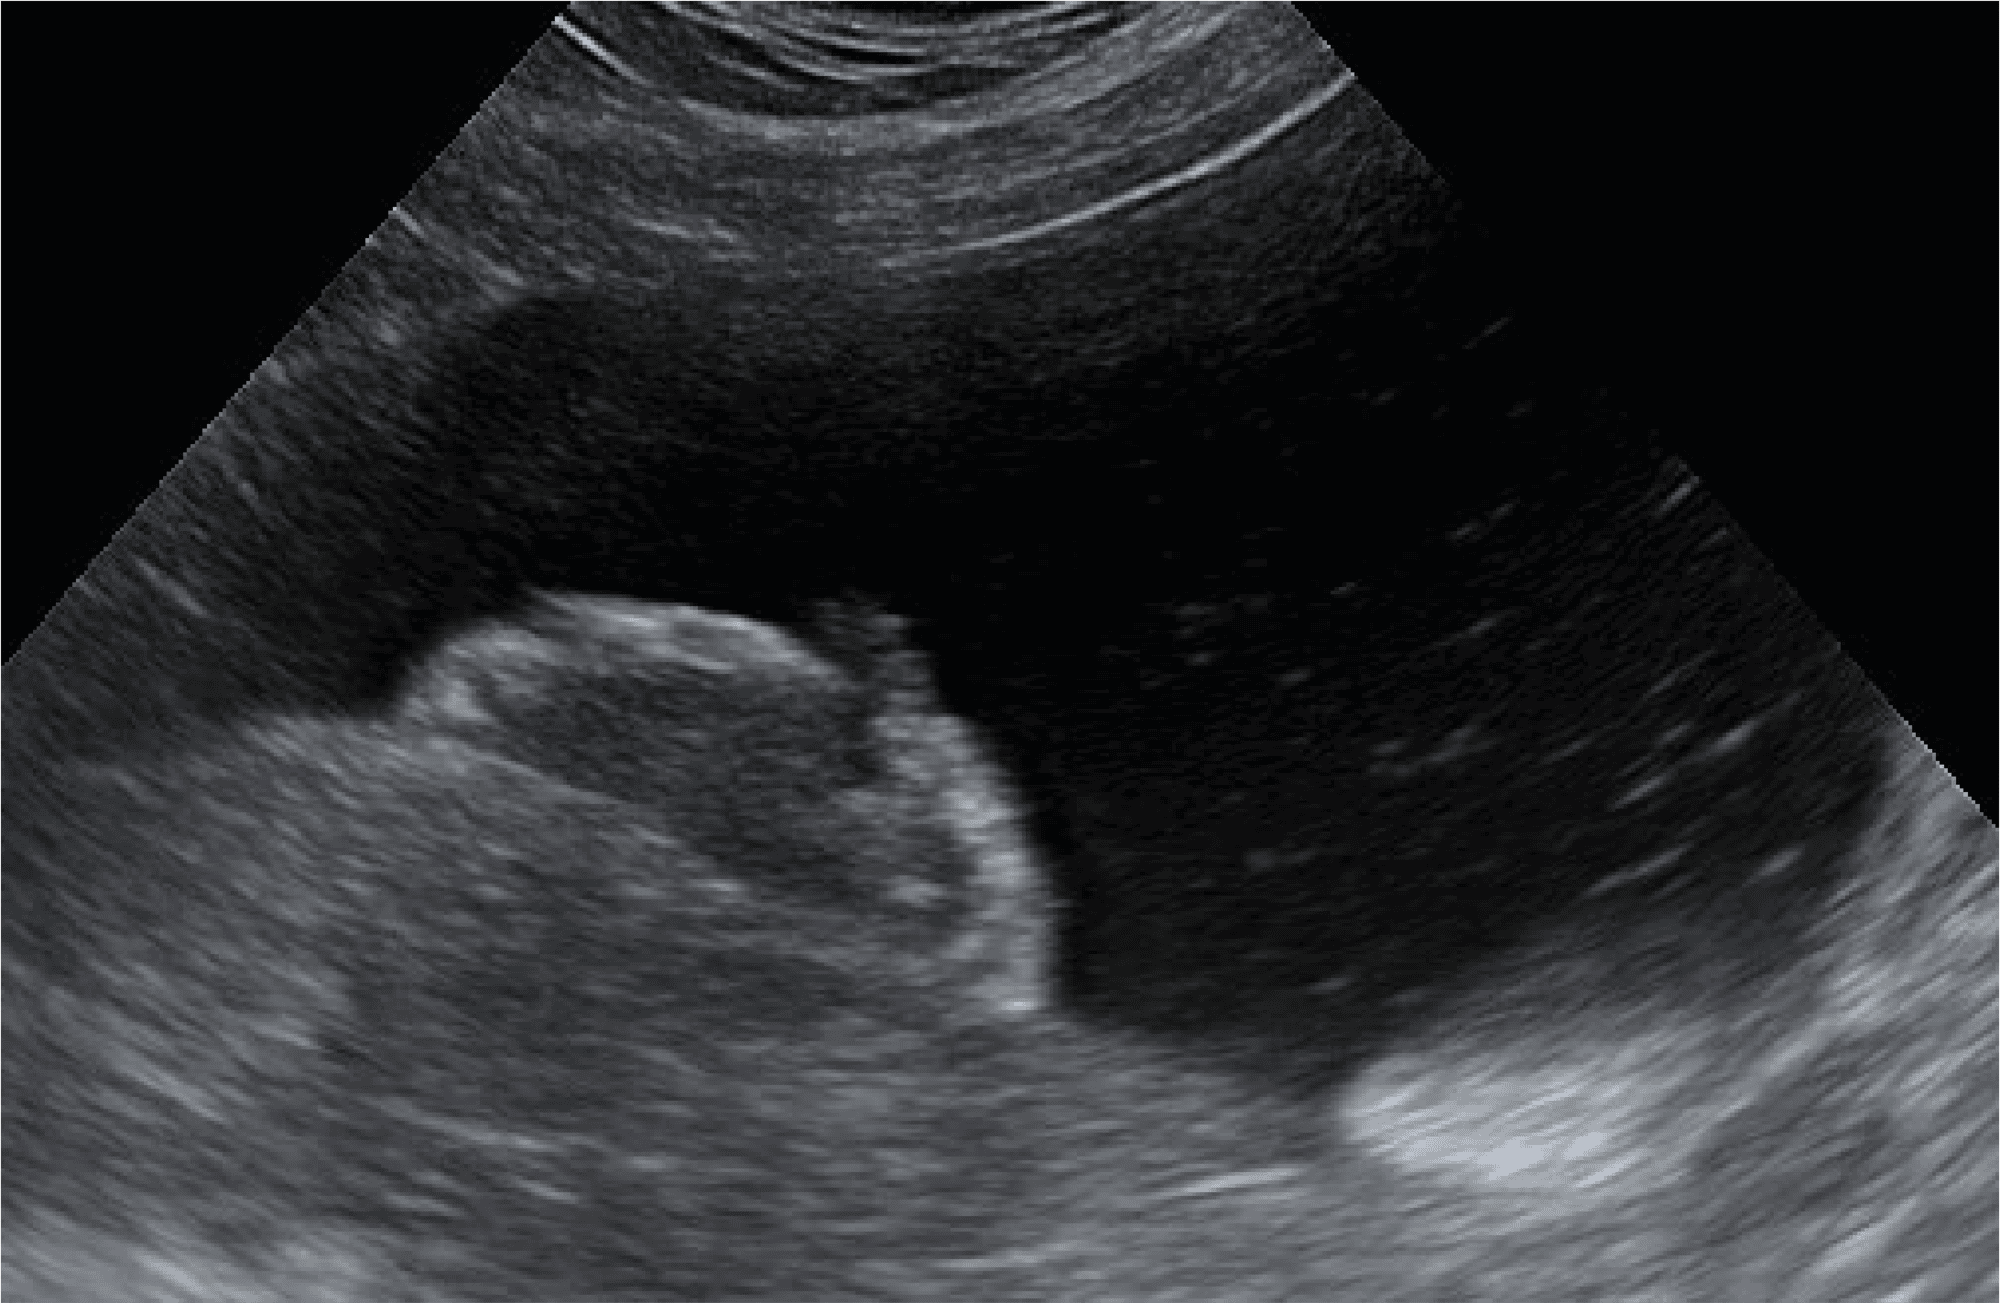

U psów zarówno nowotwory urotelialne (UCa) pęcherza moczowego i cewki moczowej, jak i raki prostaty (PCa) są wysoce złośliwymi nowotworami, które często są diagnozowane stosunkowo późno (np. w badaniu USG, Rys. 1) i mają złe rokowania. Poprzez badanie obecności mutacji V595E w genie BRAF diagnozę można postawić wcześniej, wykorzystując do badania osad moczu.